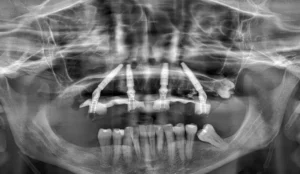

¿Quieres saber las soluciones que hay para los implantes dentales sin hueso? En este artículo te lo explicamos. Especialistas en Implantología Dental.

a tecnología de implantación ha avanzado abriendo nuevas y mejores oportunidades para que los pacientes puedan recuperar su sonrisa. En este artículo te contaremos las

La pérdida de una o varias piezas dentales puede provocar múltiples consecuencias negativas en el paciente. No solo a nivel estético, sino también en el aspecto físico.

Perder los dientes, además de afectar la autoestima y la seguridad de las personas, también genera problemas en la funcionalidad de la mandíbula, causando dificultades para comer, para hablar y